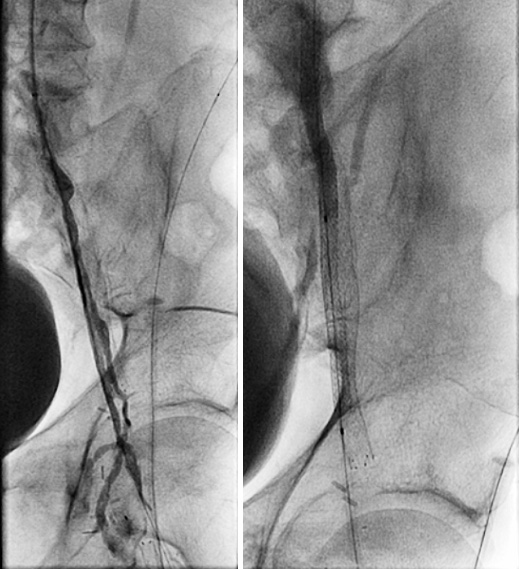

Figure 7. (left) PTA the RCFA, (right) Post PTA recoil

Figure 8. Post-stenting angiogram with double-barrel technique

We gained left femoral artery access with up-and-over technique sheath advance to the right external iliac artery. As expected, we failed to cross the right CFA occluded stent to the jailed right profunda. Ultrasound access was obtained in the right profunda femoral artery in a retrograde fashion. We probed the chronic total occlusion of the ostial segment of the right profunda and the CFA in retrograde fashion, but we could not get into the true lumen of the right external iliac. We then used the IVUS guided crossing device, “Pioneer,” and successfully crossed the occlusion of the right common femoral artery. The entire crossing passage was outside the existing occluded CFA stent and inside the wall of the CFA. The lesion was pre-dilated with a 5×20 mm PTA balloon and then a 6×40 mm PTA balloon. Despite the good release of the lesion at 10 atm, there was severe recoil post dilation of 80% residual stenosis. We inserted a 7×80 mm Zilver PTX DES stent into the right common femoral artery, followed by a balloon expandable short stent at the iliofemoral junction for persistent recoil.

The completion angiogram showed excellent results, with the initial 100% chronic total occlusion of the common femoral artery and profunda femoral vessels reduced to under 30%, and the terminal right external iliac 60% reduced to less than 30%. The entire new stent was deployed in double-barrel fashion alongside the occluded R CFA old stent.  The patient healed her nonhealing right AKA stump wound within three months post intervention. Eighteen months later, recurrent vague stump pain with suboptimal arterial duplex US led to another angiogram (Figure 8) that confirmed continued patency.